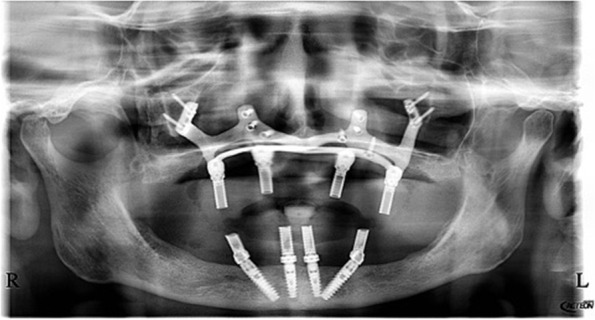

Fig. 7.

The postoperative panoramic view showed the proper placement of the screws and the implant